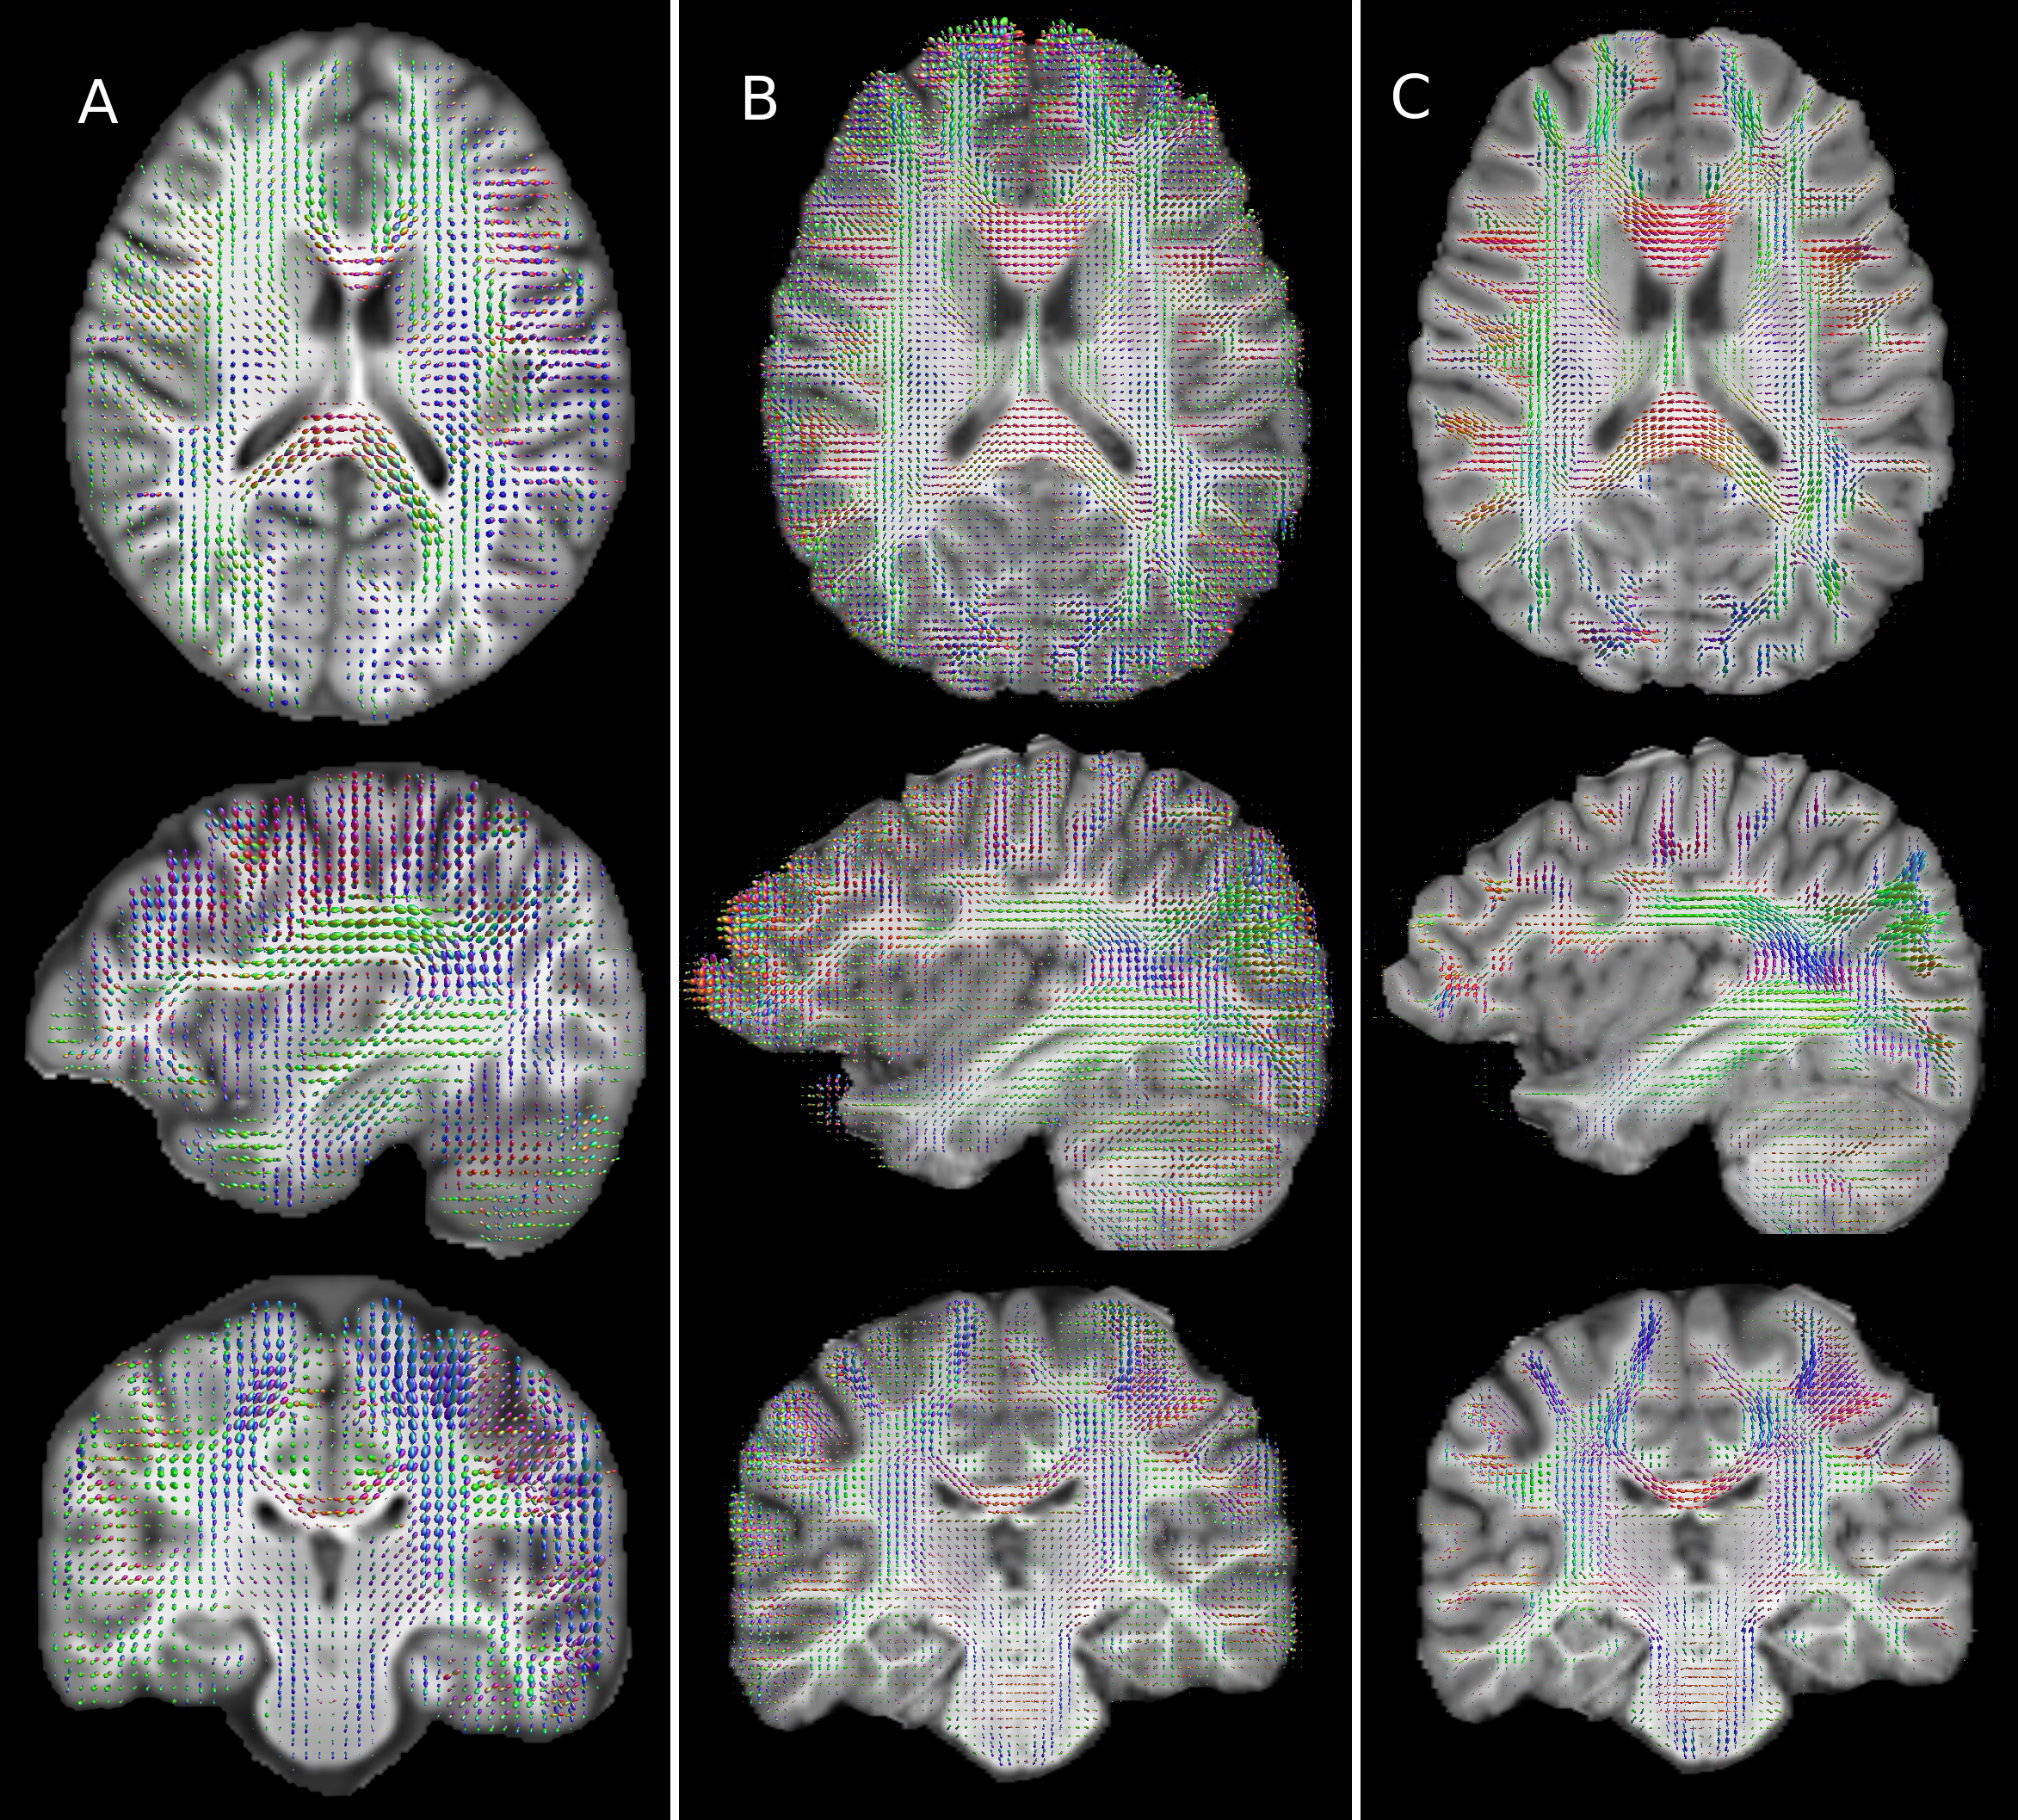

Refer to caption

Figure 3: Comparison of fibre orientation distribution plots computed in the same representative subject for the ULF (A), HF with 30 directions and one shell (B), and HF with 253 diffusion volumes across 6 shells (C). Substantial blurring is apparent in A, with margins of WM structures being less well defined and adjacent structures averaging together. Conspicuously this leads to large assigned fibre populations in GM, particularly in highly convoluted regions. Comparing A with C shows there is generally good correspondence between ULF and the gold standard measurement. Comparing B and C shows the significant impact of a reduced direction count on an otherwise high SNR measurement, with B showing smaller bundles having erroneously large lobes, and grey matter with significant anisotropy that is not corroborated by C.